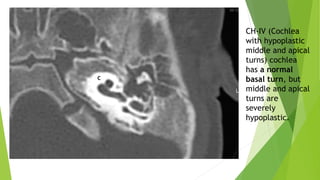

d- CH-IV (Cochlea with hypoplastic

middle and apical turns)

The cochlea has a normal basal turn,

but middle and apical turns are severely hypoplastic and located

anterior and medially rather than in their normal central position.

The labyrinthine segment of the facial nerve is usually located

anterior to the cochlea rather than in its normal location

CH-IV (Cochlea

with hypoplastic

middle and apical

turns) cochlea

has a normal

basal turn, but

turns are

severely

hypoplastic.